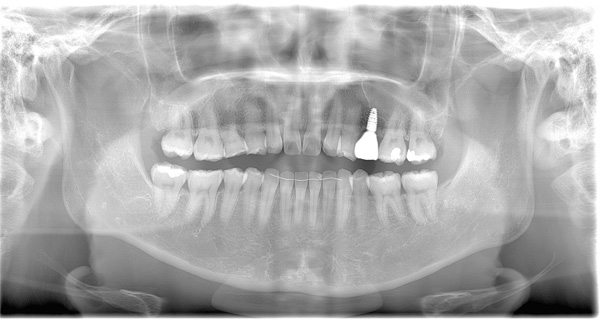

| 年代・性別 | 50代 男性 |

|---|---|

| 主訴 | 前医で前歯を抜かなければならないがインプラントはできないと言われた |

| 治療期間 | 約12ヶ月 |

| 費用 | 600,000円 |

| 治療内容 | インプラント、骨造成、結合組織移植、セラミック修復 |

| 治療に伴うリスク | インプラント周囲炎 セラミックの破折、脱離 |